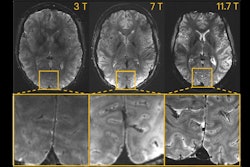

Axial view of the human brain at the same resolution (0.2 mm in-plane resolution and 1 mm slice thickness), with an identical acquisition time of around four minutes but at different magnetic field strengths. At 3 tesla and at 7 tesla (only three such machines in France and around 100 worldwide), the precision and sharpness are lower. At 3 tesla, a "grainy" cloud prevents the anatomical structures of the brain from being clearly delineated. At 7 tesla, when zooming, the level of detail at this resolution is reduced. At 11.7 tesla, the scan provides more signals and greater contrasts between biological tissues, which allows more detailed exploration of the brain. All images courtesy of CEA.